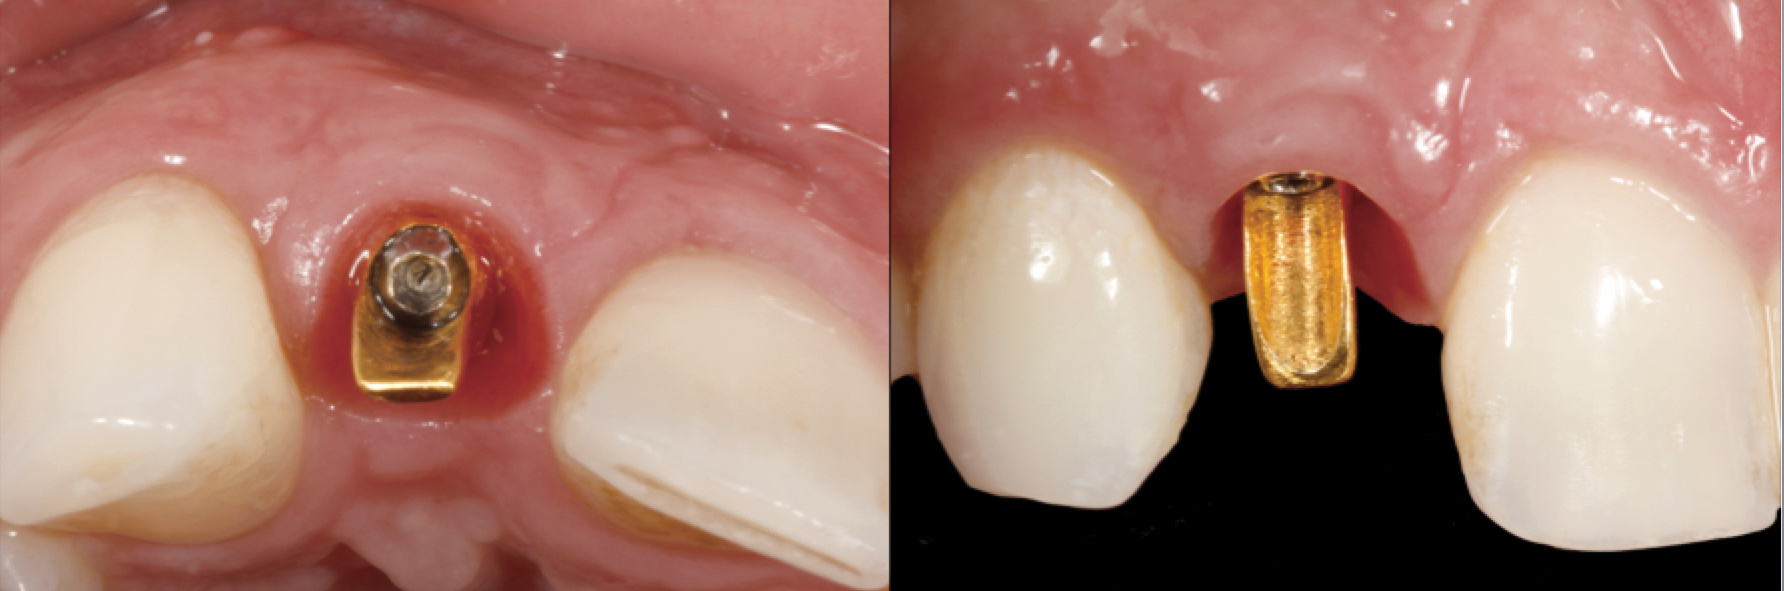

Problem: The implant is placed too facial with significant recession on the midfacial aspect of the abutment and/or crown; the implant is healthy and the patient has a high smile line with an intermediate to thick periodontal phenotype (Figure 1 and Figure 2).17-19

Solution: Decoronate the implant by placing a surgical cover screw on it and allow the soft tissues to migrate over the coronal aspect (implant decoronation).8,20,21 A few weeks later, perform the second-stage uncovering of the implant and place a flat profiled healing or custom abutment to redirect the submergence profile or angle of the provisional crown.22 After maturation of the peri-implant mucosal soft tissues several weeks later, make the final impression and construct the definitive restoration with compensatory flat subgingival contours to allow midfacial soft-tissue stability.

Fig 1. Midfacial recession can affect the esthetics of a smile and lead to an unsatisfactory outcome.

Fig 2. The cause for midfacial recession is excessive labial implant placement. Secondary to poor placement is overcontouring of the implant abutment.

Fig 3. A patient presented with a high smile line and midfacial recession of the maxillary right lateral incisor as evidenced by the increased tooth length compared with the contralateral lateral incisor.

Figure 3

Fig 4. Intraoral view of tooth No. 7 with the gingival zenith more apical than the adjacent central incisor and canine tooth.

Figure 4